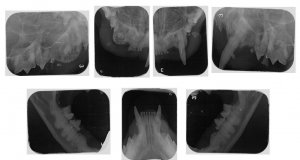

Ja, sie hat FORL - und sie hat absolut keine Symptome gezeigt. Ich hänge den Behandlungsbrief und die Röntgenbilder hier mal an.

Tja, diese Diagnose hat mich nun doch einigermaßen schockiert, muss ich sagen. Ich hätte Stein und Bein darauf geschworen, dass Hermine kein FORL hätte, weil sie absolut überhaupt keine Schmerzanzeichen gezeigt hat. Sie hat vollkommen normal gefressen, sie hat nie gespeichelt, nie den Kopf beim fressen schief gehalten und nie das Futter wieder aus dem Mäulchen fallen lassen. Und trotzdem waren zwei Wurzeln schon komplett weggefressen.

Anhänge

Befund.JPG

170,5 KB

· Aufrufe: 46

Röntgenstatus1.JPG

67,1 KB

Röntgenstatus2.JPG

43,4 KB

· Aufrufe: 40